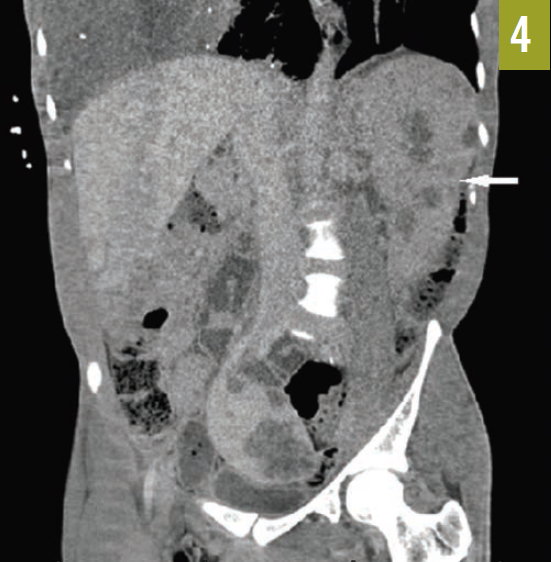

The patient had an established diagnosis of Proteus syndrome. On physical examination, he exhibited a cerebriform soft tissue nevus on the right palm (Figure 3), which is the result of a proliferation of collagenous tissue in the dermis and is highly specific for Proteus syndrome. Also noted was unilateral hypertrophy of his right hand and foot. A CT scan of the abdomen revealed massive splenomegaly, extending from the diaphragm to the pelvis (Figure 4).

Figure 4. A CT scan of the patient’s abdomen showed massive splenomegaly (arrow).